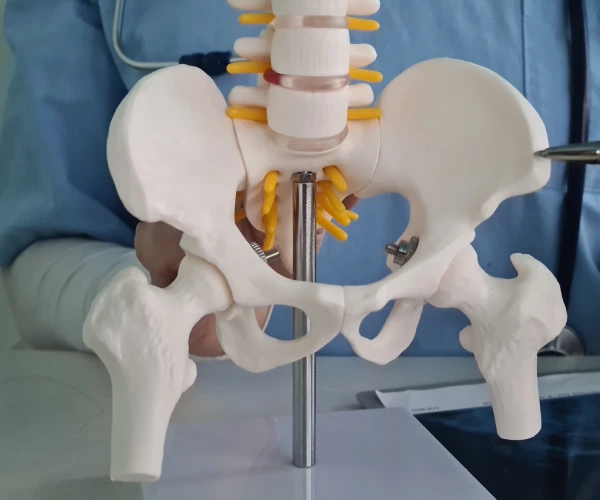

¿Qué es la Cirugía de Cadera?

¿Cuándo necesitas una Cirugía de Cadera?

¿Cómo la Cirugía de Cadera mejora tu calidad de vida?

Beneficios de la Cirugía de Cadera

¿Qué incluye la valoración para Cirugía de Cadera?